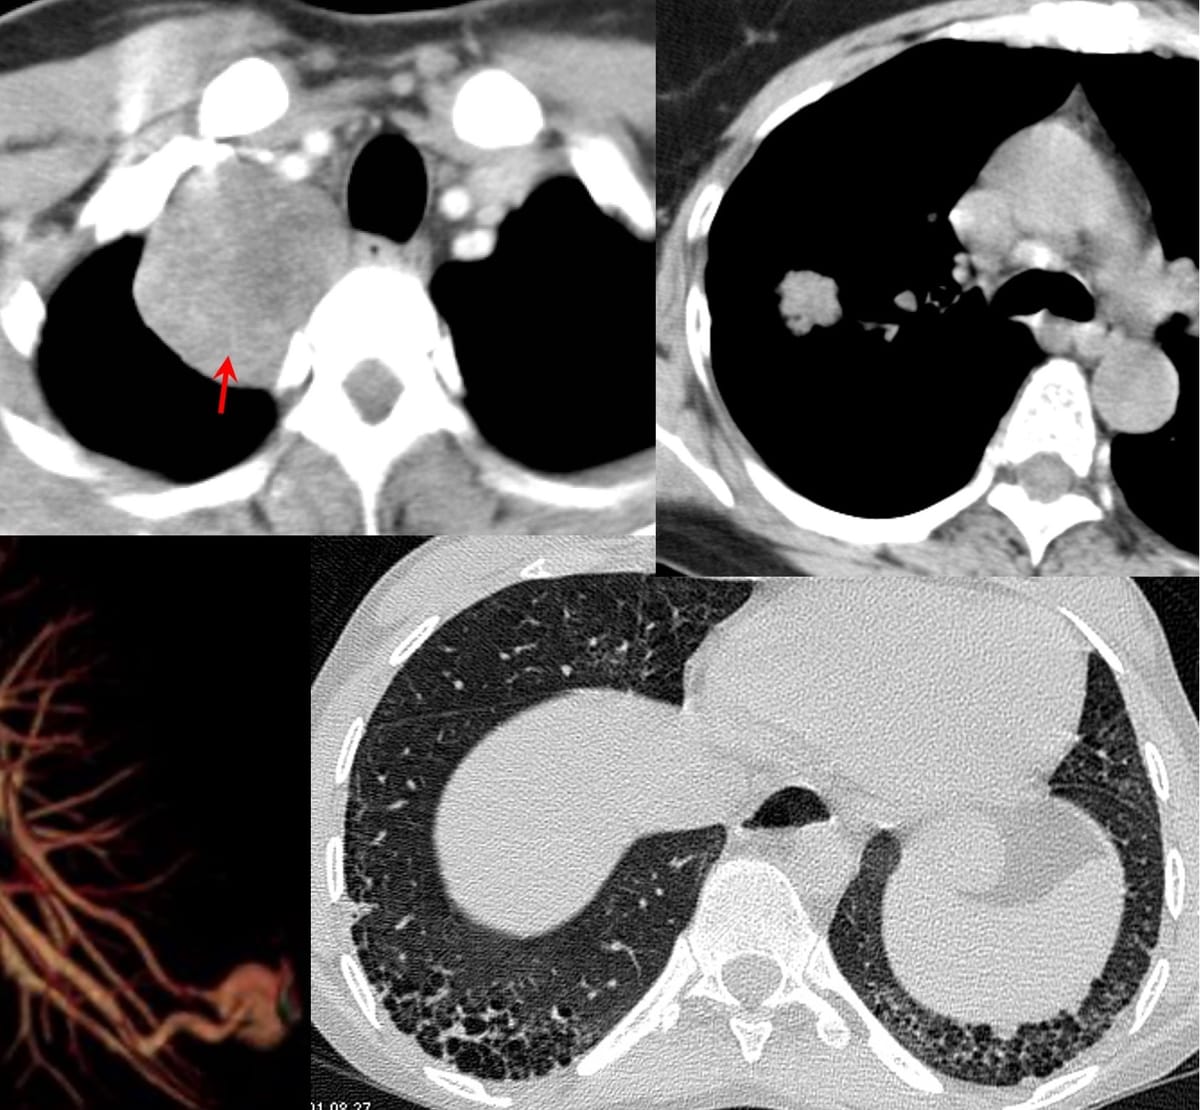

With 116 Cases, 29 Snippets, 15 Lectures, the 4-years old site now is a comprehensive resource on chest radiology, mainly CT chest. Along with regular Cases of the Day, the idea is to keep abreast of all the new developments, while continuing to add to the foundations and basics.